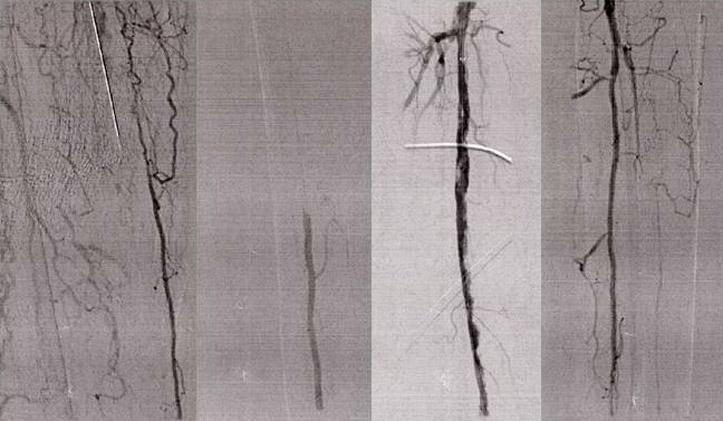

• Former smoker with high blood pressure, hyperlimidemia, prostate cancer, NIDDM, CAD with prior right occluded artery percutaneous coronary intervention (PCI) in 2011

• S/P left CFA endarterectomy in 2016 but severe left calf claudication due to long-calcified SFA CTO

• Wingman™ catheter used to traverse densely calcified SFA/AK popliteal CTO

• PTA SFA/pop to deliver re-entry device; DCB

• Final angiograms show distal runoff